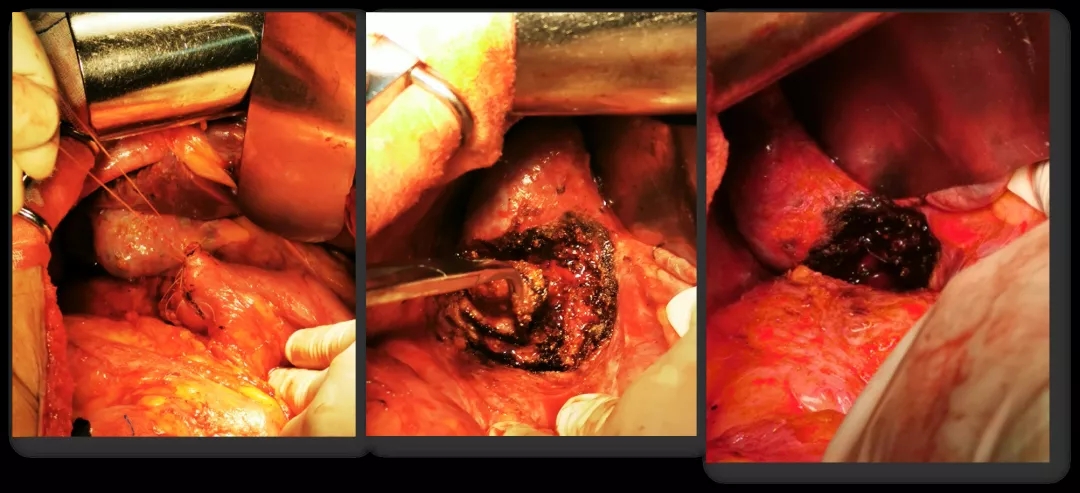

2016.10.26行三次减瘤术(乙状结肠部分切除侧侧吻合+腹盆腔减瘤+腹膜后淋巴结切除),术后无肉眼残留。

术中所见

再次减瘤术

术后病理

朱笕青教授对这则病例进行总结:该病人自发病以来,生存期超过13年,得益于再次减瘤术和新型抗肿瘤药物的开发与进展(如PARP抑制剂);再次减瘤术可使部分铂敏感复发卵巢癌的患者获得生存获益,R0切除是关键;我们体会,一旦判断肿瘤复发,越早实施手术越好,肿瘤负荷小更容易做到完全切除。